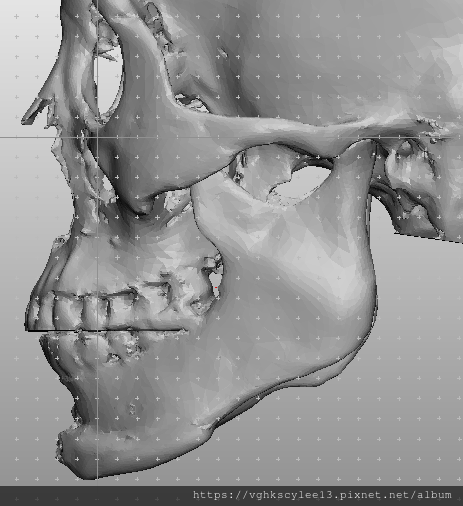

下圖:不對稱下巴骨架,透過列印技術可以做出調整下巴歪斜的假體組合。

歪斜下巴調整性假體設計

下圖範例:歪斜不對稱下巴經3D導航客製化導航矯正性假體

(下圖)3D模擬後工程師版的設計下巴假體的外型。

經過李醫師醫師對客戶外型的判斷,修改工程師的設計,建議更改後的假體模型(下圖)

(上圖)經過李醫師醫師對客戶外型的判斷,修改工程師的設計,建議更改後的假體模型。所以嘍,醫師的美感與專業度必須要做判斷,3D列印只是精準工具但是必須有專業醫師的判斷才可以完美!